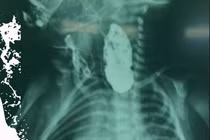

Bệnh viện Phụ Sản Hà Nội phối hợp với Bệnh viện Nhi Trung ương thực hiện đặt máy tạo nhịp tim ngay tại phòng sinh cho em bé bị tim bẩm sinh nặng, được chẩn đoán Block nhĩ thất độ III từ trong thai kỳ.